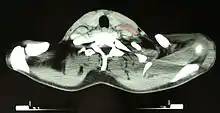

Diagnosis

Hodgkin lymphoma must be distinguished from noncancerous causes of lymph node swelling (such as various infections) and from other types of cancer. Definitive diagnosis is by lymph node biopsy (usually excisional biopsy with microscopic examination). Blood tests are also performed to assess function of major organs and safety for chemotherapy.[22] Positron emission tomography (PET) is used to detect small deposits that do not show on CT scanning. PET scans are also useful in functional imaging (by using a radiolabeled glucose to image tissues of high metabolism). In some cases, a gallium scan may be used instead of a PET scan.[23]